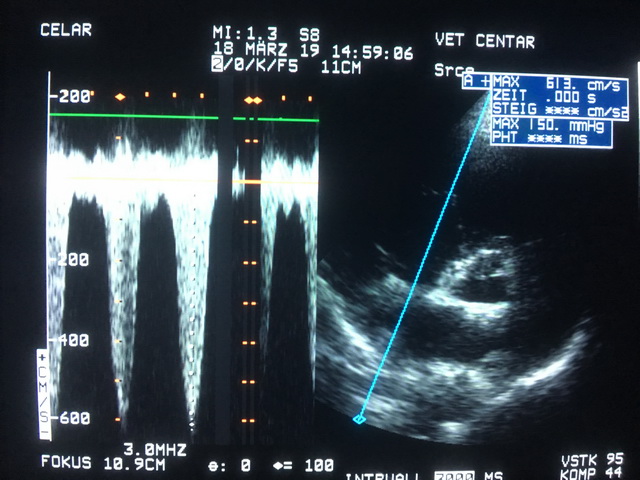

Nakon utvrđene dijagnoze, neophodno je sprovesti dodatna ispitivanja tako što se načini rendgenski snimak pluća i ultrazvučni pregled srca i glavnih plućnih arterija (slika 3 i 4). Ovi rezultati omogućavaju tačnu procenu ozbiljnosti infekcije i pravilan izbor daljeg načina nege i lečenja.

Povišenje plućnog pritiska, koje predhodi slabosti srca, može se na vreme uočiti kompetentnim ultrazvučnim pregledom. Zbog toga su neophodne kardiološke kontrole svih pacijenata inficiranih ovim parazitom, bez obzira na početni stadijum bolesti i bez obzira na primenjeni način lečenja (slika 6).